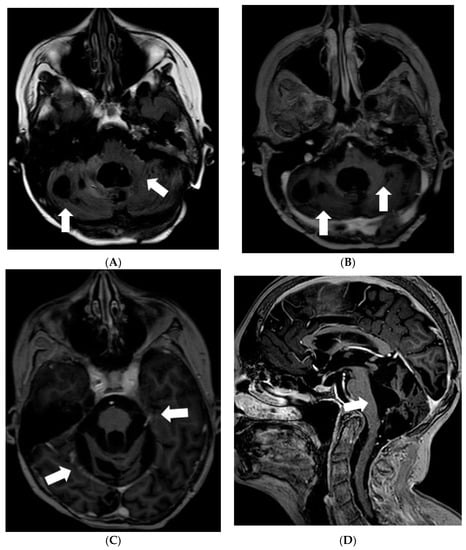

Later the girl was treated in Klaipeda University Hospital. In May 2013, a follow-up MRI demonstrated enlarged cystic lesions in the subarachnoid spaces with compression of the brainstem and the cerebellum and vivid leptomeningeal enhancement extending to the spinal canal (Figure 4). T2W/FLAIR/FS images revealed heterogenous, slightly hyperintense lesions with hypointense foci in the subarachnoid spaces. Clinically, ataxia and weakness of the legs worsened. Partial resection of the neoplastic masses from premedullary cisterns and the IVth ventricle was performed. It was decided to administer chemotherapy with temozolomide. Gradually, the condition of the patient improved.

Figure 4.

Follow-up MRI of the brain 2 years after the onset of symptoms (May 2013): (A) Axial T2W/FLAIR/FS, (B) axial, and (C) sagittal T1W postcontrast images demonstrate enlarged cystic lesions in the subarachnoid spaces causing compression of the brainstem and the fourth ventricle and vivid leptomeningeal enhancement extending to the spinal canal.